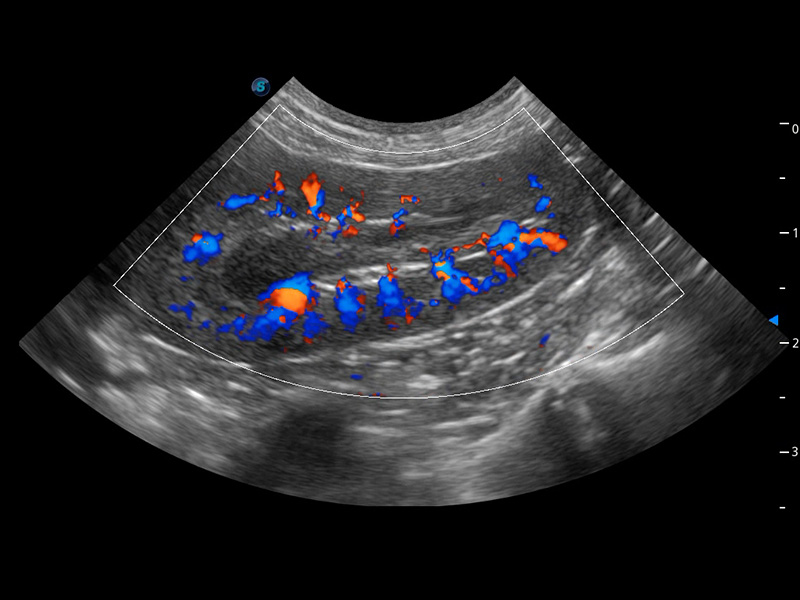

优异的基础图像

(犬)四腔心血流

(犬)肾脏血流